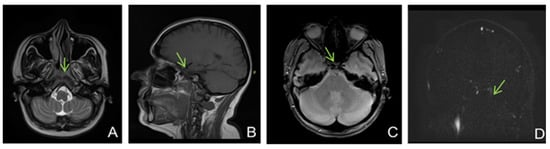

Figure 5. Non-enhanced MRI (at onset): ((A)—T2 axial, (B)—T1 sagittal, (C)—T2* axial, (D)—venous TOF coronal) shows unremarkable parenchyma and absence of flow in cavernous sinuses on TOF imagesFive months later, the patient came back to our clinic complaining of paroxysmal episodes of altered state of consciousness with language disorders such as verbal barrage followed by disorientation. An EEG was performed, showing a low-voltage background path, weakly modulated in spindles in the left derivations, reactive when opening the eyes, and rare isolated degraded peak-wave complexes, thus concluding that the patient was experiencing focal onset impaired awareness seizures; she was then started on antiepileptic treatment with oxcarbazepine 300 mg twice daily. She also was psychiatrically examined due to emotional lability confirming the diagnosis of depression and allowing antidepressant treatment to be started.

A brain MRI (Figure 5) showed flow asymmetry at the level of the cavernous sinuses, left more than right, coupled with fluid accumulation in the left mastoid cells, whilst cerebral parenchyma had morphology and signals within normal limits, thus establishing the diagnosis of bilateral (left > right) cavernous sinus thrombosis. The patient was started on continuous heparin infusion followed by treatment with acenocoumarol.

The six-month follow-up MRI identified persistent left maxillary sinusitis and cavernous sinus asymmetry but with an improved flow in the left one. Additionally, after 2 weeks of subcutaneous low-weight heparin, the panel for thrombophilia was requested and a protein C and S deficit was found, with the other tests (lupus anticoagulant, antithrombin III, factor V Leiden, IgM and IgG antiphospholipid antibodies, IgM and IgG anti-cardiolipin antibodies, IgM and IgG anti beta-2 glycoprotein I, p-ANCA, and c-ANCA) being within normal values. Thus, thrombophilia was diagnosed and the indication of lifelong anticoagulation established.

The patient continues to present a depressive disorder that improves under treatment and rare paroxysmal seizures with intermittent speech impairment. She was noted to be otherwise stable, with no further neurological sings.